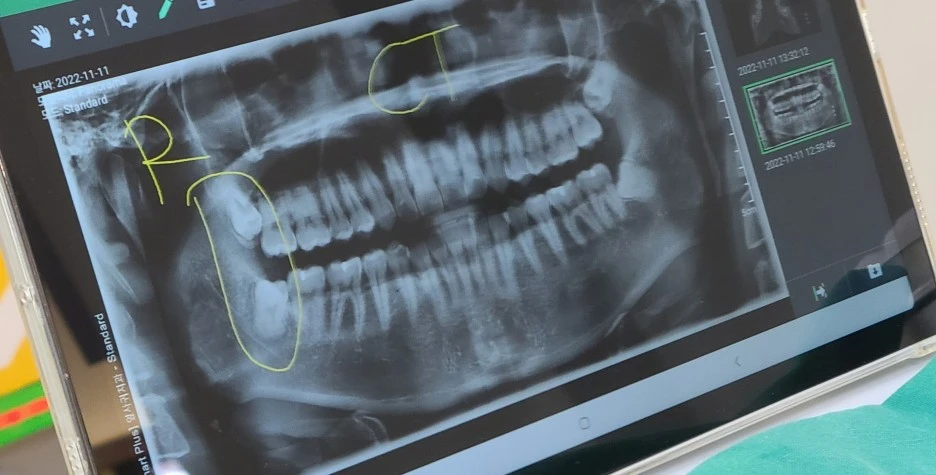

나의 치과 방사선, 사랑니 위치가 정말 엉망이다.

사랑니 발치하기 전에 X-ray부터 찍었는데 정말 가관이었다. 오른쪽을 보니 살짝 마중 나온 우측 하악의 사랑니, 그리고 뼈에 박혀 뽑는 것이 쉽지 않을 수도 있겠다는 우측 상악의 사랑니가 있었다. 일단 나는 아프니까 둘 다 뽑겠다고 했는데, 사실 더 큰 문제는 왼쪽이었다. 좌측 상악의 사랑니는 뼈와 완전히 붙어있었고 아예 파묻혀 있는 정도였다. 그리고 하악의 경우 잇몸에 파묻혀 있고 삐딱하게 누워있어 언제든지 좌측 하악의 어금니를 괴롭힐 수 있었다. 즉 좌측 하악의 사랑니에 염증이 생길 경우 어금니 쪽으로 쉽게 염증이 옮겨갈 수 있다는 뜻이었다. 비록 사랑니를 전부 뺄 마음은 있었지만 우측보다 더 심한 좌측을 보니 한숨만 절로 나왔다. 사랑니가 조금만 더 곧게 자랐다면 나의 수십만 원은 아낄 수 있었을 텐데...